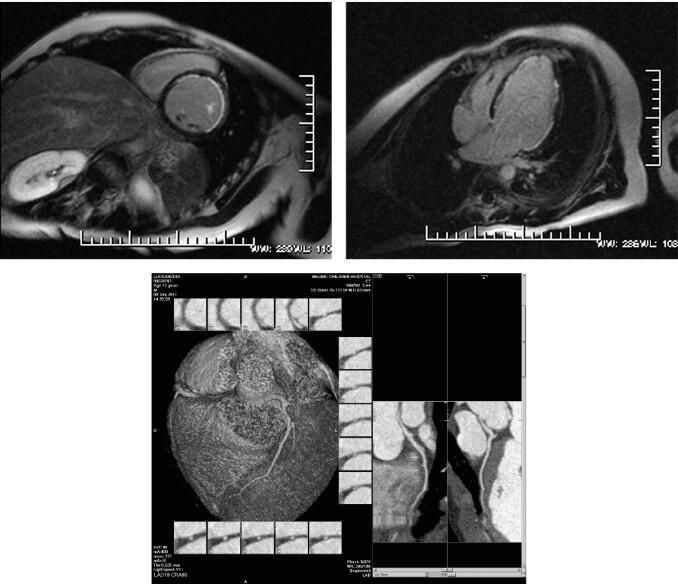

磁共振成像参数应用1.5T场强的MRI仪(Magnetom Sonata,Siemens),患者取仰卧位,头先进,32通道心脏表面线圈,心电门控,采用黑血脉冲序列获得体轴横断位图像,然后行四腔心、两腔心长轴和两腔心短横断位梯度回波电影、静息态心肌灌注采用两腔心短轴和四腔心层面,应用钆喷酸葡胺对比剂,按0.2mmol/kg体重注射。灌注扫描的对比剂流率为5ml/s,总量8ml。延迟强化扫描注射对比剂的流率为2ml/s,总量14ml。通常在心肌灌注扫描后8~10分钟进行延迟扫描。整个心脏MRI检查方案见表1。影像学检查见图1。

图1 冠状动脉左主干起源于右窦

冠状动脉CTA:左主干起自右窦,走形于右室流出道与主动脉之间,前降支走形于前室间沟;管壁规则,左主干管腔受压,余前降支管腔通畅,未见明显狭窄或扩张改变。

MRI表现:心内结构未见明显异常,左室增大;心脏电影显示左室前壁、侧壁及心尖节段运动减低,各瓣膜收缩舒张未见明显异常,未见返流信号;心肌静息灌注显像见左室前壁、侧壁及心尖心内膜下灌注减低,心肌延迟强化序列显示对应节段延迟强化。